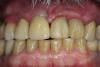

After 4 months of healing and integration of the bone around the implant, the digital workflow was initiated to develop the abutment and treatment plan. Another analog impression was made with an impression post and polyvinyl impression. The laboratory scanned the impression and digitized it to create the emergence profile of the milled titanium abutment and the final restoration (Figure 10 and Figure 11). The patient had a considerably thick soft-tissue profile, allowing a milled titanium abutment. The decision to use a titanium abutment was based on the patient's occlusion and propensity to fracture teeth or restorations. The virtual model was gray because the scanner does not recognize the color of the analog impression. The virtual final abutment and crown were approved and fabrication completed. The final restoration met the patient's esthetic values and his ability to function (Figure 12 and Figure 13).

Fig 10. Titanium abutment proposal.

Figure 10

Fig 11. Final crown proposal.

Figure 11